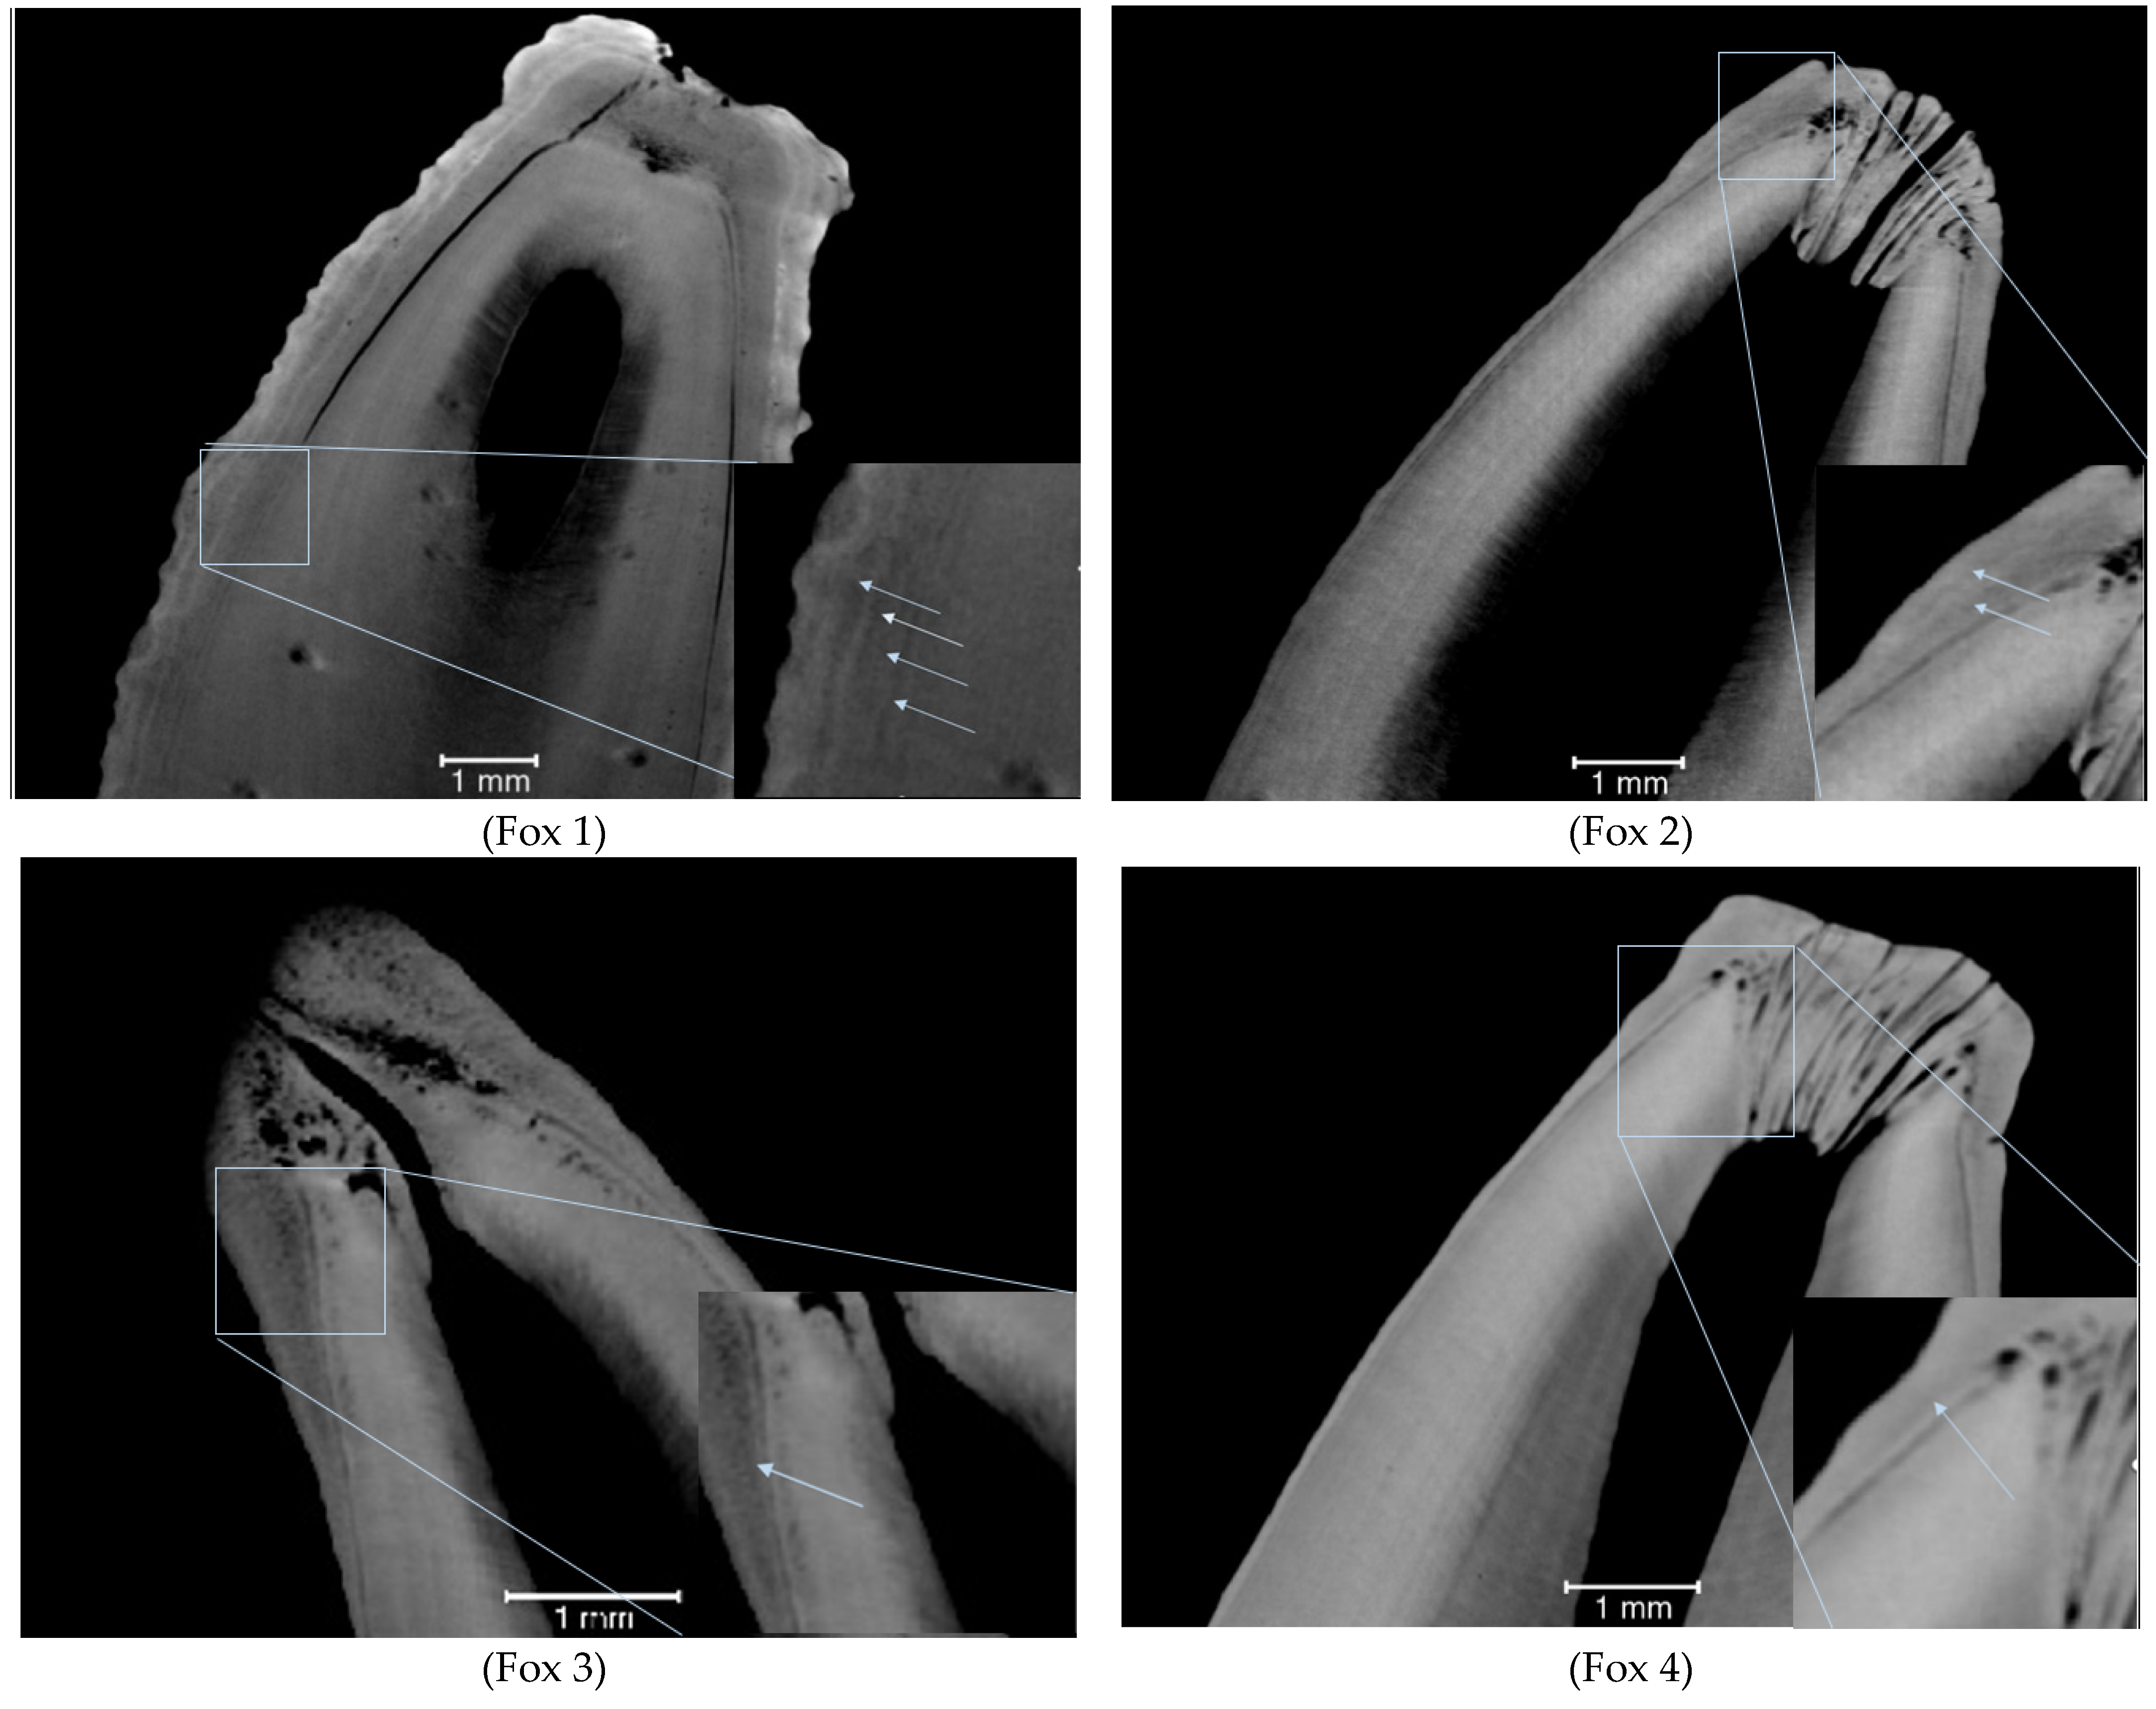

| Fox 1 (838–839) | 4.9 | 4 |

| Fox 2 (948–949) | 1.5 | 2 |

| Fox 3 (1051–1052) | 1.7 | 1 |

| Fox 4 (3113–3114) | 1.7 | 1 |

| Fox 7 (689–690) | 4.6 | 5 |

| Fox 8 (707–708) | 2.8 | 2 |

| Fox 9 (3420–3421) | 2.2 | 3 |

| Fox 10 (741–742) | 6.8 | 7 |

| Fox 11 (4505–4506) | 4.3 | 3 |

| Fox 12 (705–706) | 1.6 | 2 |

| Fox 13 (693–694) | 3.8 | 3 |